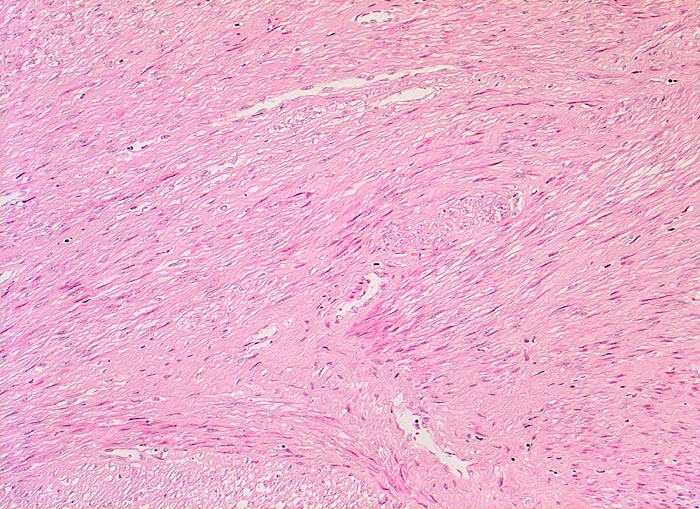

Myome imponieren makroskopisch typischerweise als runde, scharf begrenzte und nicht bekapselte Knoten. Die Schnittfläche ist weiss mit wirbliger Struktur. Mikroskopisch ist der Tumor aufgebaut aus Bündeln (=Faszikeln) spindelförmiger Zellen mit reichlich dunkel-eosinophilem Zytoplasma und an den Enden abgerundeten länglichen, zigarrenförmigen Kernen. Zell- und Fasergehalt sind sehr variabel. Degenerative Veränderungen wie Verkalkungen (> 4280), hyaline Nekrosen, Einblutungen, Homogenisierung des Kollagens, Ödem oder myxoide Degeneration und Zystenbildung (> 4279) kommen häufig vor. Manche gutartigen Leiomyome können ein einzelnes Malignitätskriterium aufweisen (vermehrte Mitosen, hohe Zellularität, deutliche Zellatypien oder Nekrosen). Falls mehr als eines dieser Kriterien vorhanden ist, handelt es sich differentialdiagnostisch um einen leiomyomatösen Tumor mit unsicherem Malignitätspotential (STUMP=Smooth Muscle Tumor of Uncertain Malignant Potential) oder um ein Leiomyosarkom. In seltenen Fällen lässt sich die Dignität nicht sicher bestimmen.

• Zwei scharf begrenzte Knoten im Myometrium bestehend aus Bündeln glatter Muskulatur.

• Variabler Anteil Fibrose (Kollagenfasern).

• Keine signifikanten Zellatypien. (signifikant=bereits in der Übersichtsvergrösserung erkennbar).

• Keine Mitosen.

• Keine Tumornekrosen.